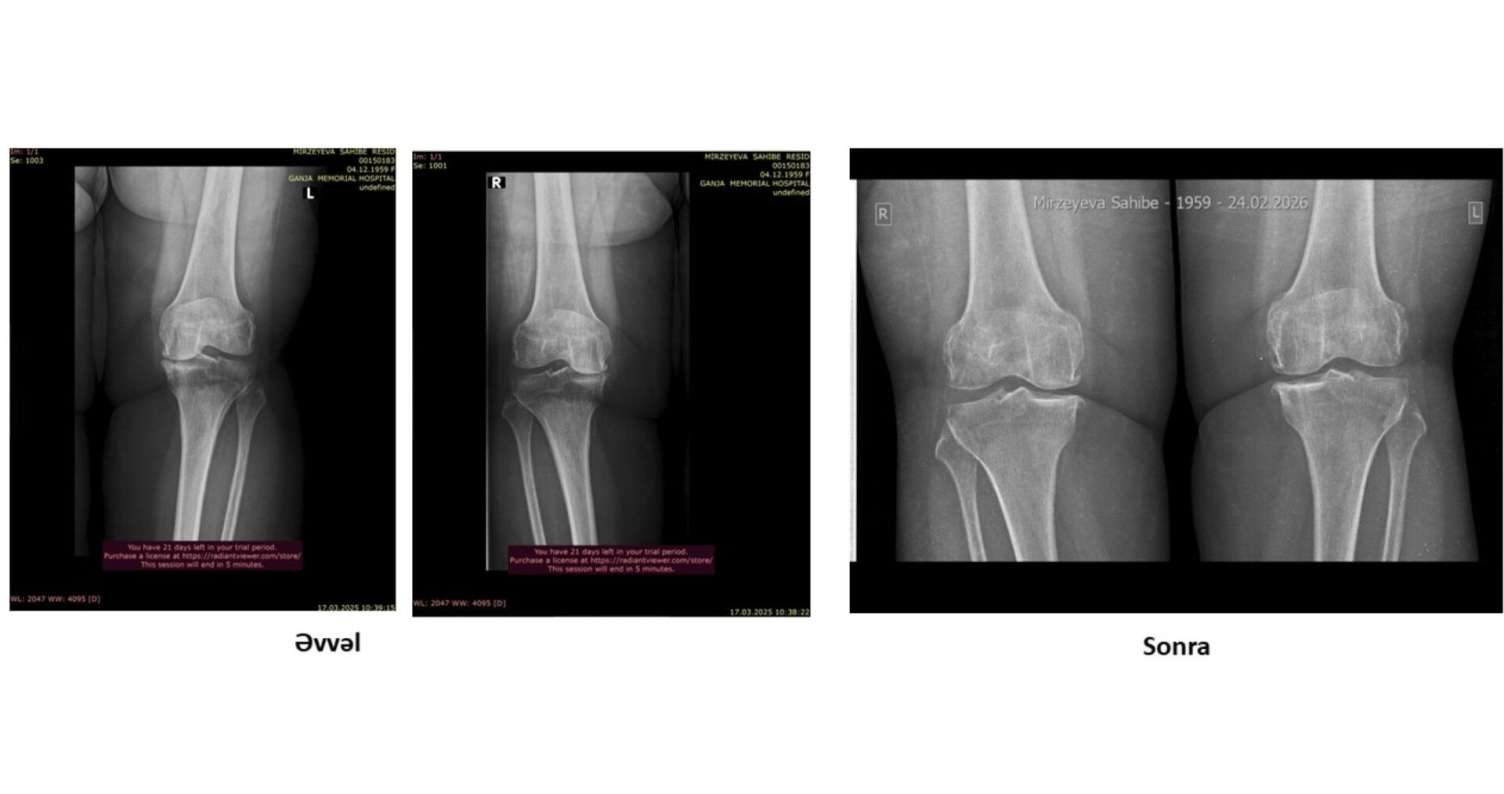

Həkimlər